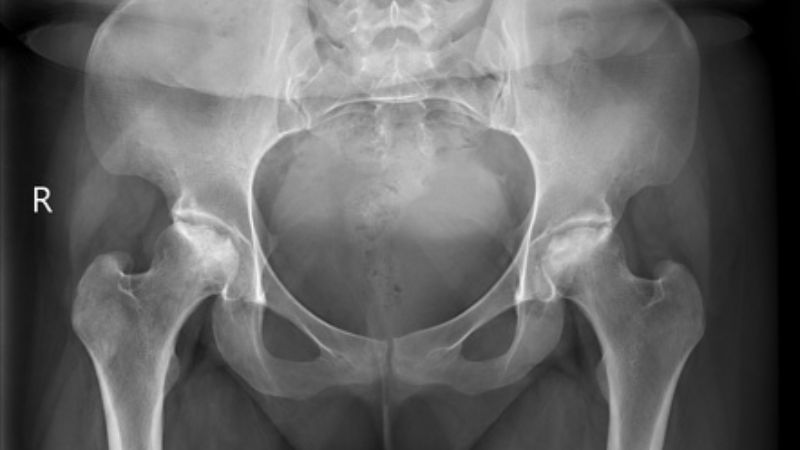

Đánh giá lâm sàng có thể giúp bác sĩ định hướng bệnh nhân có khả năng mắc hoại tử vô mạch, tuy nhiên để làm rõ chẩn đoán thì cần làm thêm một số các xét nghiệm sau:

- Chụp X-quang: giúp khảo sát các bất thường ở xương như gãy, biến dạng...

X-quang có thể giúp chẩn đoán hoại tử vô mạch